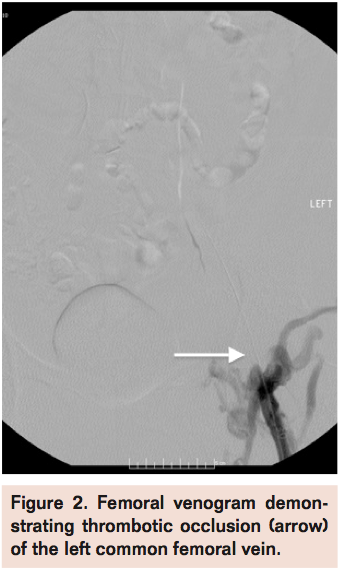

Selective bilateral venography was scheduled and the patient placed in prone position with ultrasound-guided bilateral popliteal vein access. A 7 Fr Ansel sheath (Cook Medical) was placed in the left popliteal vein and a 5 Fr Ansel sheath in the right popliteal vein. Selective venogram of the left popliteal vein confirmed occlusion of the left common femoral vein with extensive collateral network (Figure 2). Selective venogram of the right iliac vein demonstrated normal flow into the IVC (Figure 3) with normal appearance and positioning of the IVC, filter free of filling defects with brisk flow.